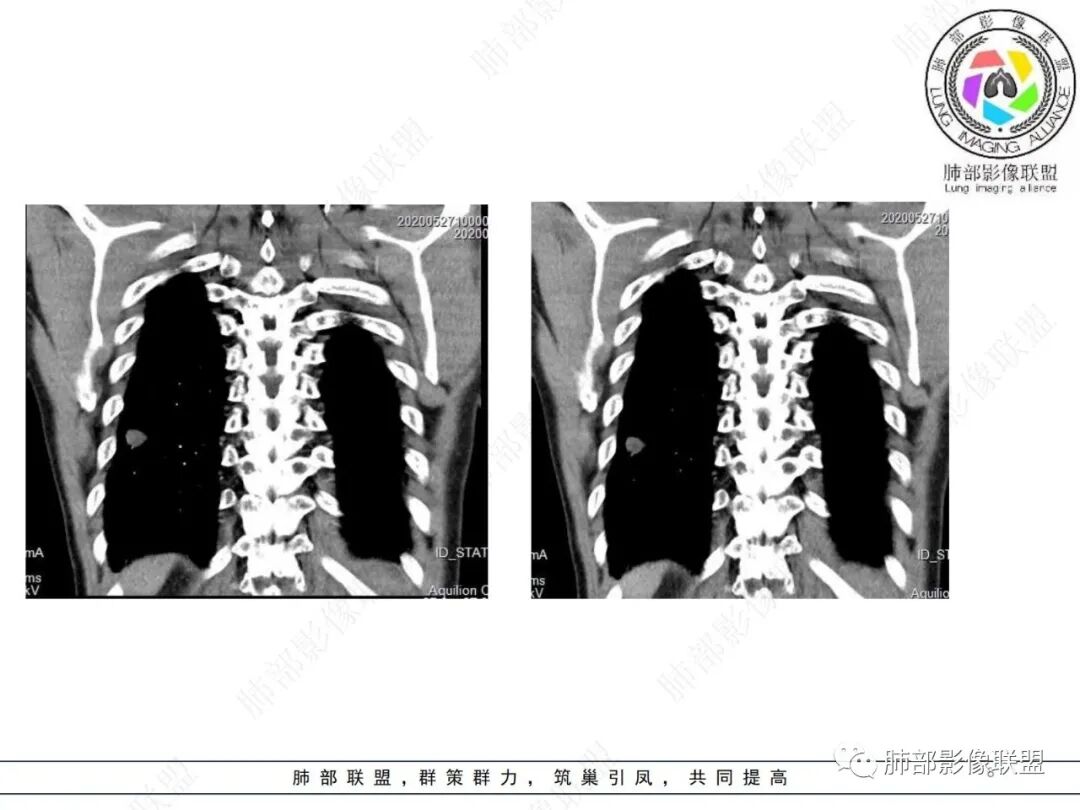

此病例中结节,与支气管无关系,边缘清晰,形态规则,缺乏张力,未见典型的分叶及毛刺,病灶周围磨玻璃为部分容积效应所致,肺门纵隔未见肿大淋巴结,良性病变可能性较大,肺部的良性肿瘤中,最常见的是错构瘤,其次是硬化性肺细胞瘤(PSP),第三是孤立性纤维性肿瘤(SFT)。

肺错构瘤

常表面光滑,可有浅分叶或无分叶,无毛刺,对周围肺组织无牵拉;常挂枝头(挂在肺动脉枝头上),很少到达胸膜。出现脂肪成分,或者典型的爆米花样钙化几乎可以确诊,软骨型错构瘤因软骨组织多,强化弱。平滑肌型错构瘤增强有一定强化。病灶周围边界清楚,常有很低密度的黑晕。

综上所述,错构瘤可能性最大